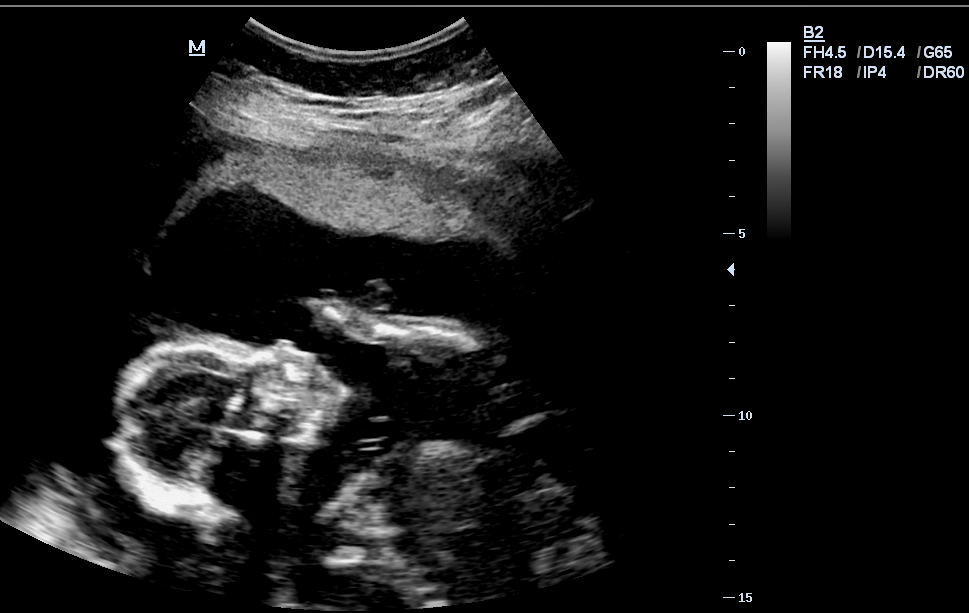

We had our scan this morning. It was hard to get good pictures because he was curled up facing my spine, and I have an anterior placenta (not sure if this interferes with getting pictures, the tech just pointed it out).

The tech took all the measurements but didn't tell me any of them other than his heart rate (142) and weight (13 oz). Now just anxiously awaiting our regular 20-week appointment tomorrow afternoon.